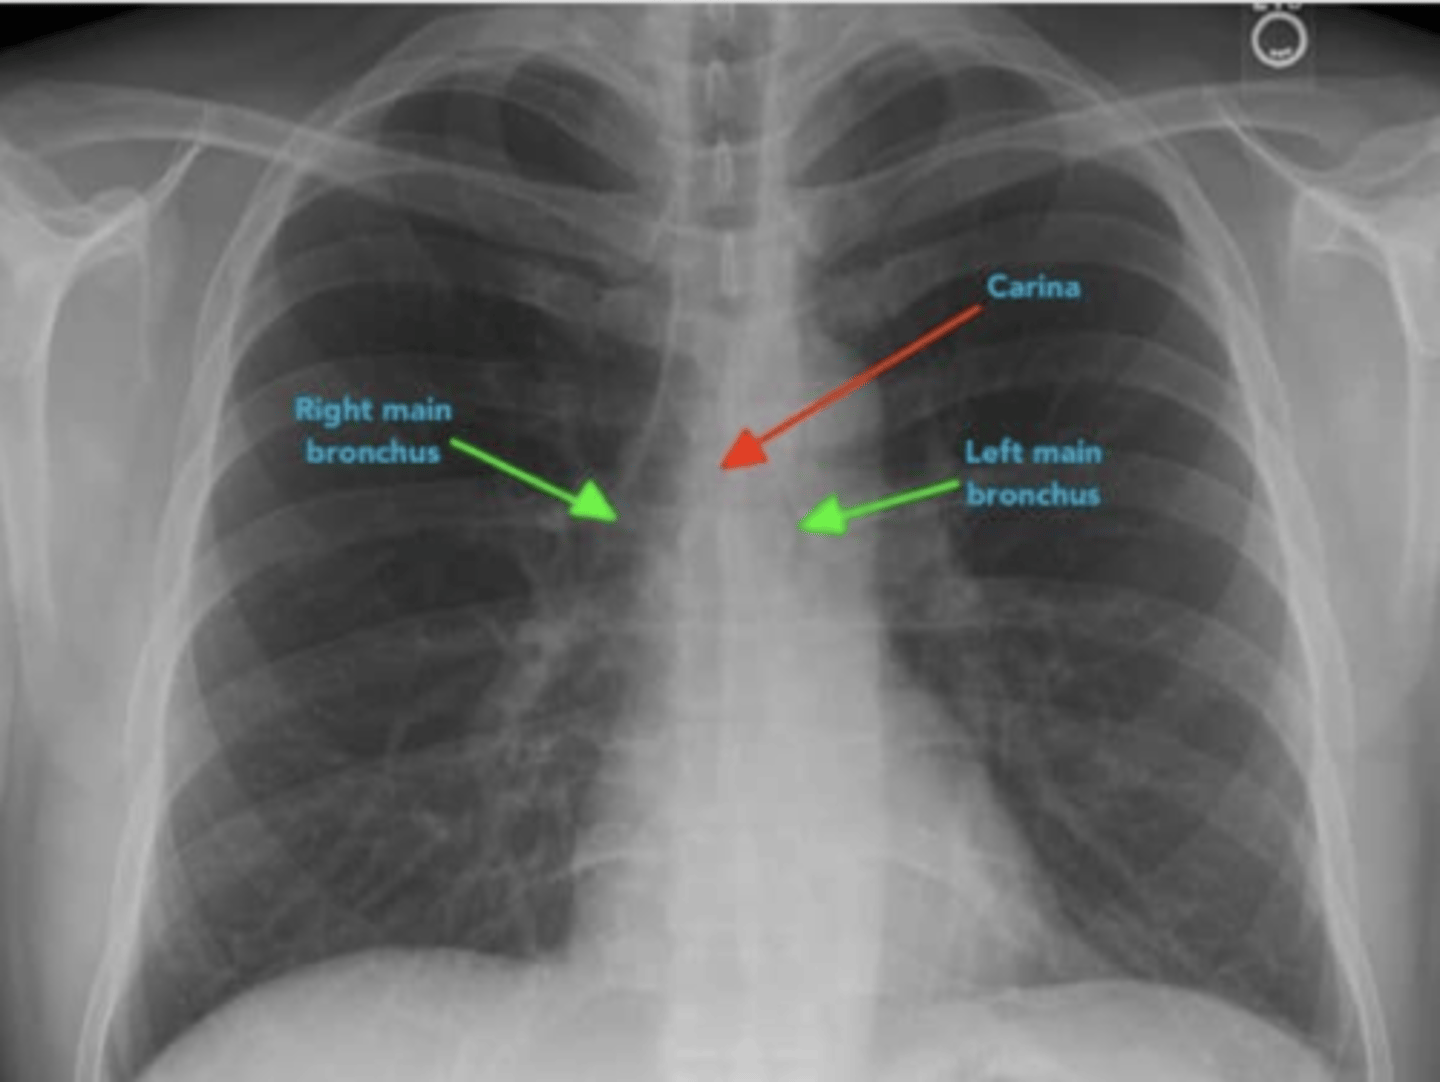

1.Carina and bronchi

⚬The carina is cartilage situated at the point at which the trachea divides into the left and right main bronchus.

•On appropriately exposed chest X-ray, this division should be clearly visible.

•The carina is an important landmark when assessing nasogastric (NG) tube placement, as the NG tube should bisect the carina if it is correctly placed in the gastrointestinal tract.

2. The right main bronchus is wider, shorter and more vertical than the left main bronchus.

•As a result of this difference in size and orientation, it is more common for inhaled foreign objects to become lodged in the right main bronchus.